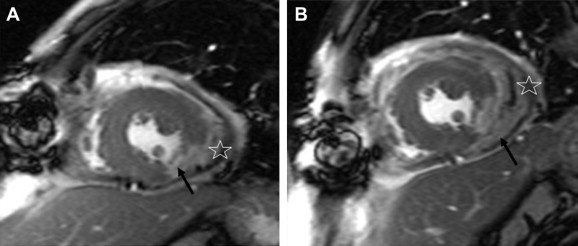

A 49-year-old man presented to our emergency department with chest pain and diaphoresis that had been intermittently occurring for 1 day. His heart rate and blood pressure were 120 beats/minute and only 79/41 mmHg, respectively. An electrocardiogram revealed an ST-segment elevation in the inferior and lateral leads. Elevation in serum creatine kinase and troponin I levels was observed. An emergent coronary angiogram showed total occlusion of the posterolateral branch of the right coronary artery. At that time, no coronary intervention was performed. Owing to the discrepancy between the deteriorating hemodynamics and the coronary lesions, emergent echocardiography was performed, which indicated massive pericardial effusion with cardiac tamponade. Pericardiocentesis was performed, and an outflow of fresh blood was noted. Thus, LVFWR was suspected, and an emergent operation was performed. After sternotomy, severe bloody oozing was observed from the lateral wall of the left ventricle. No major myocardial tear was found. An oozing postinfarct LVFWR was diagnosed. Under intra-aortic balloon pump support, the rupture site was repaired with BioGlue (Cryolife Inc.) applied to a 5 cm × 10 cm diameter Teflon felt, using a sutureless technique. The patient was discharged in a good condition 2 weeks after the operation. One month later, cardiac MRI revealed an infarcted area at the posteroinferior wall of the left ventricle and an asymptomatic localized pericardial effusion between the left ventricle and the Teflon felt (Fig. 1A). Pseudoaneurysm formation in the left ventricle was detected. The follow-up MRI performed after 2 weeks revealed an enlargement of the localized pericardial effusion (Fig. 1B). A second operation was then scheduled to assess the clinical progression of the LVPA. Under cardiopulmonary bypass, ventricular fibrillation was induced and the pseudoaneurysm was extirpated. The fibrous scar tissue around the infarcted area was partially resected. The left ventricle defect was directly closed with reinforcement using Teflon felt strips (Fig. 2). The postoperative course was uneventful, and the patient was discharged home in a stable condition.

(A) The short-axis, delayed, gadolinium (Gd)-enhanced true fast imaging with ...

Figure 1.

(A) The short-axis, delayed, gadolinium (Gd)-enhanced true fast imaging with steady-state precession (FISP) image revealing a transmural hyperenhancement at the posteroinferior wall of the left ventricle (black arrow), indicating a transmural infarction. Localized leakage of the Gd contrast medium into the pericardial space is observed, suggesting pseudoaneurysm formation (asterisk). (B) The delayed, Gd-enhanced true FISP cine image obtained 2 weeks after, showing the progression of the increasing leakage of the Gd contrast medium into the pericardial space (black arrow) and the complete detachment of the Teflon felt from the epicardium (asterisk).